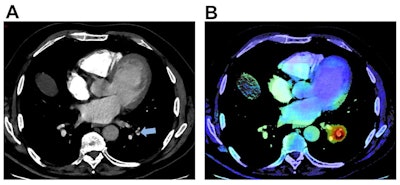

Example of an output provided by the AI algorithm (AIDOC Medical) to detect pulmonary embolism (PE). A: 64-year-old man presented with spontaneous unilateral pain in the lower limb, increased with palpation, and unilateral edema. The revised simplified Geneva score was 3 and the D-dimer dosage was positive. A contrast-enhanced CT pulmonary angiogram (CTPA) demonstrated a PE in the left lower limb (blue arrow). B: On the same cross-section, the AI algorithm highlighted the same location of the suspected PE through a color-encoded map. All figures courtesy of Dr. Alexandre Ben Cheikh and colleagues and European Radiology.

Example of an output provided by the AI algorithm (AIDOC Medical) to detect pulmonary embolism (PE). A: 64-year-old man presented with spontaneous unilateral pain in the lower limb, increased with palpation, and unilateral edema. The revised simplified Geneva score was 3 and the D-dimer dosage was positive. A contrast-enhanced CT pulmonary angiogram (CTPA) demonstrated a PE in the left lower limb (blue arrow). B: On the same cross-section, the AI algorithm highlighted the same location of the suspected PE through a color-encoded map. All figures courtesy of Dr. Alexandre Ben Cheikh and colleagues and European Radiology."Instead of replacing radiologists, AI for PE detection appears to be a safety net in emergency radiology practice due to high sensitivity and [negative predictive value], thereby increasing the self-confidence of radiologists," the authors wrote.

Clinical examples. A 71-year-old patient with a medical history of cancer and recent surgery presented with heart rate > 95 beats per minute and a borderline saturation and underwent a CTPA. The CTPA showed a segmental, sub-acute, PE in the right low limb, which was missed by the emergency radiologist during his on-call duty (red arrow). B: On the same cross-section, the PE was correctly identified by the AI algorithm (AIDOC Medical). Example of PE was correctly diagnosed by the emergency radiologist and not by the AI algorithm. Opposite example: An 85-year-old patient with a medical history of PE and a recent surgery presented with a heart rate between 75 and 94 beats per minute and acute dyspnea and underwent CTPA (C). Two segmental PEs were correctly diagnosed by the emergency radiologist but missed by the AI algorithm (white arrows).

Clinical examples. A 71-year-old patient with a medical history of cancer and recent surgery presented with heart rate > 95 beats per minute and a borderline saturation and underwent a CTPA. The CTPA showed a segmental, sub-acute, PE in the right low limb, which was missed by the emergency radiologist during his on-call duty (red arrow). B: On the same cross-section, the PE was correctly identified by the AI algorithm (AIDOC Medical). Example of PE was correctly diagnosed by the emergency radiologist and not by the AI algorithm. Opposite example: An 85-year-old patient with a medical history of PE and a recent surgery presented with a heart rate between 75 and 94 beats per minute and acute dyspnea and underwent CTPA (C). Two segmental PEs were correctly diagnosed by the emergency radiologist but missed by the AI algorithm (white arrows).In addition to confirming the high diagnostic performance of AI algorithms for diagnosing PE on CTPA exams, the study demonstrated how AI can best support radiologists, according to the researchers. The algorithm showed particular value in poor-quality examinations and by increasing diagnostic confidence via its high sensitivity and negative predictive value.